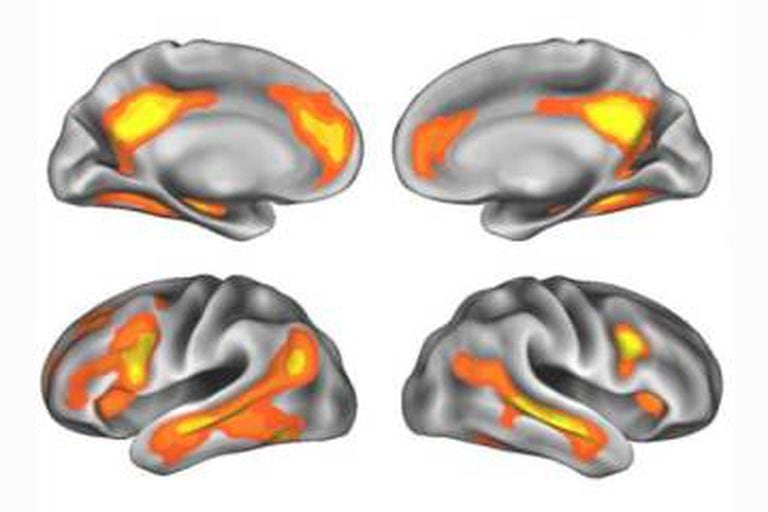

O estudo, publicado na revista Nature Neuroscience, revela profundas mudanças físicas no cérebro de todas as mulheres durante a gravidez. Em particular, detectou uma diminuição acentuada da massa cinzenta em certas áreas do córtex cerebral e não em outras. As imagens mostraram uma retirada de conexões neurais nas áreas que os cientistas relacionam com a cognição social, com a capacidade humana de se colocar no lugar dos outros, de antecipar suas intenções, de ler a mente dos outros, isto é, de sentir empatia. Mas retirada não significa perda.

Esta diminuição da massa cinzenta só acontece com as mães. As imagens do cérebro dos pais não mostraram diferenças nem em relação aos outros homens nem com as que tinham sido tomadas antes de serem pais. Também comprovaram que as áreas que perderam mais massa cinzenta foram as ativadas quando uma mãe via as imagens de seu filho, mas não quando viam imagens de outras crianças.